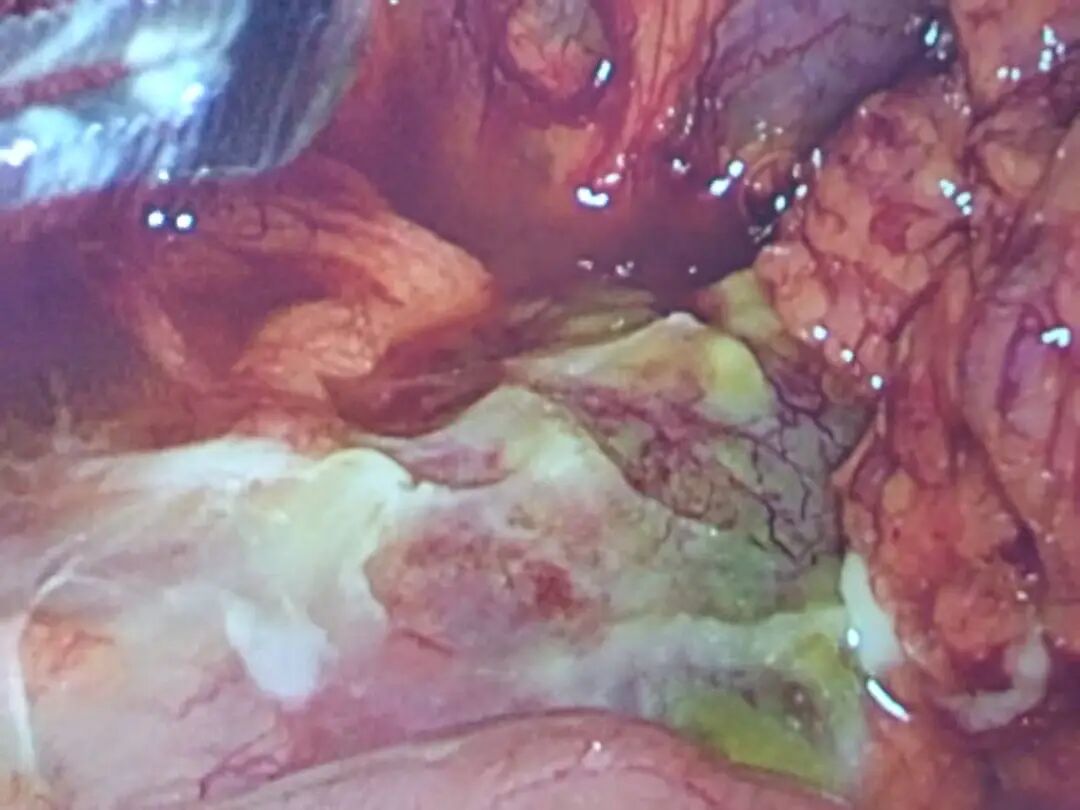

随着探头深入,视野中呈现出令人揪心的景象:腹腔内积聚着大量黄绿色脓液与脓苔,尤其在右侧肝缘、结肠肝曲及升结肠旁区域最为显著,肠间隙亦被脓液广泛浸润。

▲术中探查可见腹腔及腹膜后感染非常严重

然而,在脓液与粘连的包围下,肠壁的明确穿孔点始终隐匿难寻。腔镜下探查受阻,病情却不等人。